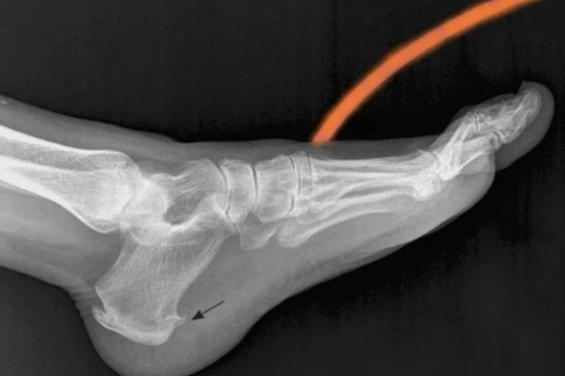

Medical Point Gaziantep Hastanesi Fizik Tedavi ve Rehabilitasyon Uzmanı Dr. Özer Erzurumluoğlu, topuk dikeni hakkında şu bilgileri verdi: "Topuk dikeni, ayak tabanındaki bağ dokusunun topuk kemiğine yapıştığı noktada kalsiyum birikmesi sonucu oluşan kemiksi bir çıkıntıdır. Genellikle sabahları, ilk adımda hissedilen keskin bir ağrı ile kendini gösterir. Bu durum, çoğunlukla ‘plantarfasiit’ adı verilen, bağ dokusunun iltihaplanmasıyla ilişkili bir tablodur. Kişi, sabah ilk adımlarında topuğunda bıçak saplanır gibi bir ağrı hisseder."